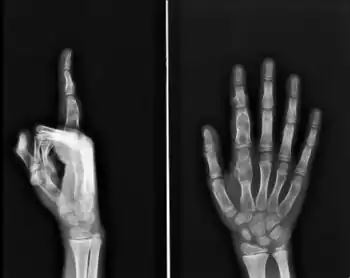

Diagnosistic tests include medical imaging.[2] Appearances on X-ray show a small lobe-shaped, dark tumor in the middle of the bone.[2] It typically contains white spots; calcified chondroid matrix (a "rings and arcs" pattern of calcification).[2] It does not extend into soft tissues.[6] Magnetic resonance imaging (MRI) and CT scan may be requested to further evaluate the tumor.[8]

X-ray: Solitary enchondroma in long bone of thigh near knee

-

Multiple (enchondromatosis) in fingers